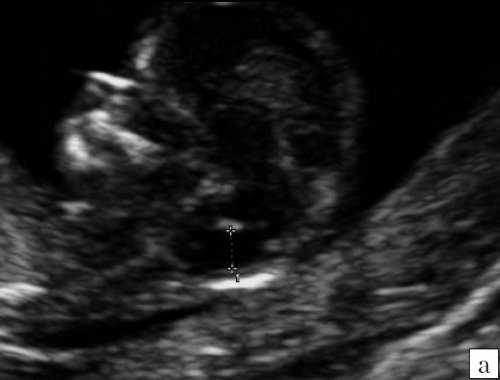

В последние годы появились публикации, посвященные возможности диагностики открытой расщелины позвоночника в I триместре беременности. Так, в 2009 г. R. Chaoui и соавт. [4] было предложено оценивать интракраниальное пространство, которое измеряется в среднесагиттальном скане и представляет собой не что иное, как IV желудочек мозга. Этот необходимый скан выводится в обязатель ном порядке для корректного измерения толщины воротникового пространства и оценки носовых костей плода в срок 11-14 недель беременности. Были созданы процентильные таблицы зависимости размера интракраниального пространства от копчико-теменного размера (КТР) плода. Для врачей практического здравоохранения, занимающихся скринингом I триместра беременности важно знать, что это среднее значение диаметра интракраниального пространства при КТР 45 мм должно быть более 1,5 мм, а при КТР 84 мм - более 2,5 мм. Исследования показали, что интракраниальное пространство при наличии у плода открытой расщелины позвоночника уменьшается [4, 5].

Как сказано выше, имеет значение и измерение ножек "осьминожки", так среднее значение диаметра нижней ножки, т.е. IV желудочка в зависимости от КТР в срок 11-14 недель варьирует от 1,5 до 2,5 мм (рис. 4).

Рис. 4. Измерение и взаимоотношение ножек "осьминожки" - ствола мозга и IV желудочка у плода, беременность 12 недель.

Измерение ножек "осьминожки".

Красный цвет - диэнцефалон (таламус), со стволом мозга (верхняя ножка) и IV желудочком (нижняя ножка); желтый цвет - большая цистерна головного мозга; синий цвет - воротниковое пространство.